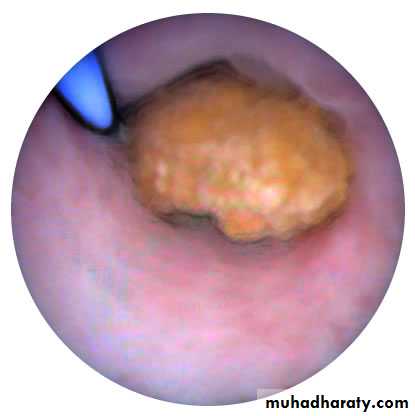

History of Hematuriabladder tumor (stageTa-T1)